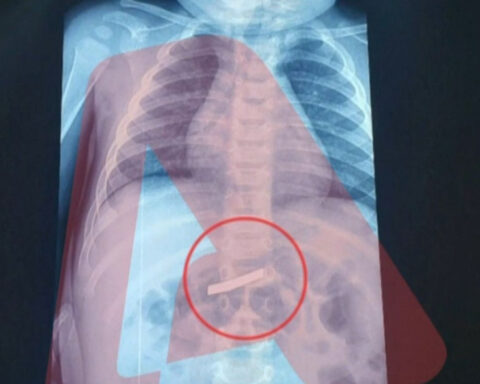

Περιπέτεια για 3χρονο στην Αθήνα έπειτα από κατάποση ξυραφιού

Ο 3χρονος βρίσκεται εκτός κινδύνου. Ένα σοβαρό περιστατικό σημειώθηκε το πρωί της Τετάρτης, όταν ένα παιδί μόλις τριών ετών οδηγήθηκε στο νοσοκομείο Παίδων στην Αθήνα, καθώς είχε καταπιεί ξυράφι. Οι γονείς ενημέρωσαν άμεσα τους γιατρούς για το συμβάν, με το ιατρικό προσωπικό